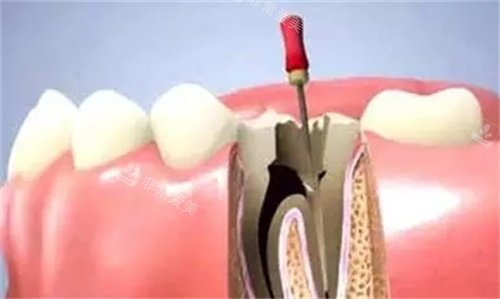

根管治疗过程模型展示图